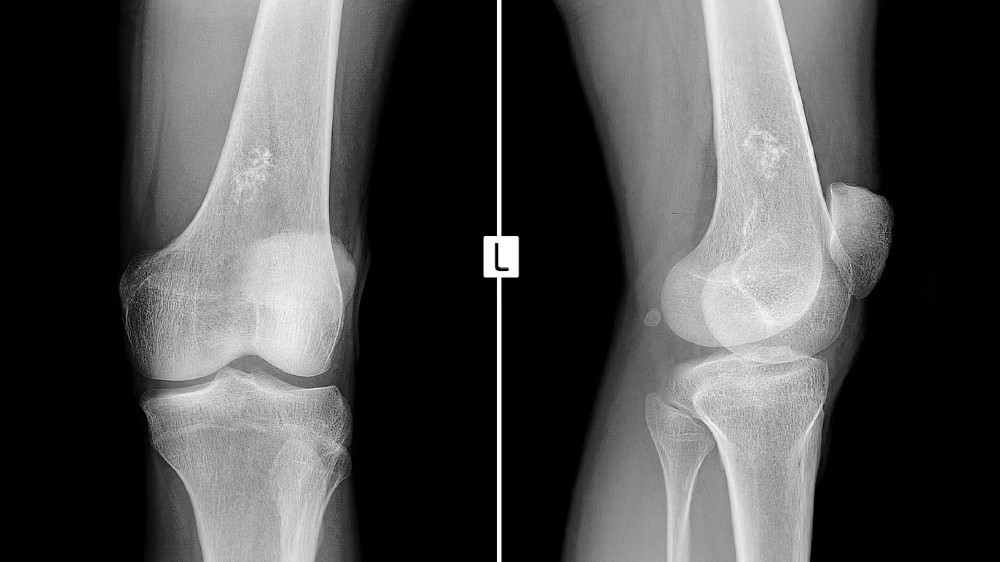

及早識別 尤文肉瘤(骨肉瘤)症狀 有助於及時介入和度身訂造的治療。專門診斷包括血液檢驗、影像研究(如 MRI、PET 掃描)和活體檢查,有助於確診和設計有效的治療策略。及時的診斷可改善預後並開啟創新治療的大門,例如先進的新陳代謝治療,其目的在於擾亂葡萄糖依賴性腫瘤的新陳代謝通路。